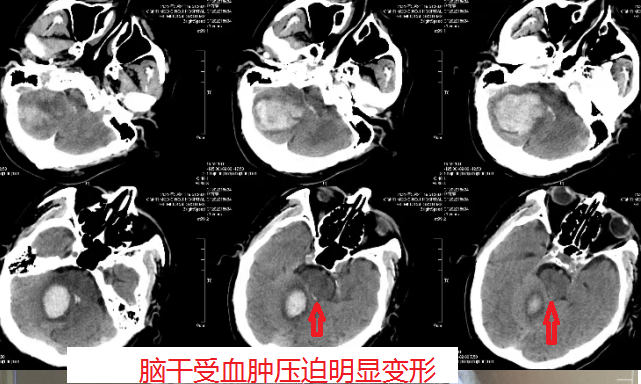

老年男性患者,72岁,患者于入院前大约三个半小时突然出现头痛、头晕,恶心呕吐,伴有肢体无力,被家属运至我院急诊科,行头部CT检查明确诊断:小脑出血,小脑半球出血量巨大,压迫脑干,随时有死亡的危险。

手术采取显微镜下小骨窗微创开颅手术的方式进行,血肿清除很彻底,术中出血少,副损伤小。

病人目前病情稳定,神清语明,双侧肢体活动正常,运动协调性良好。